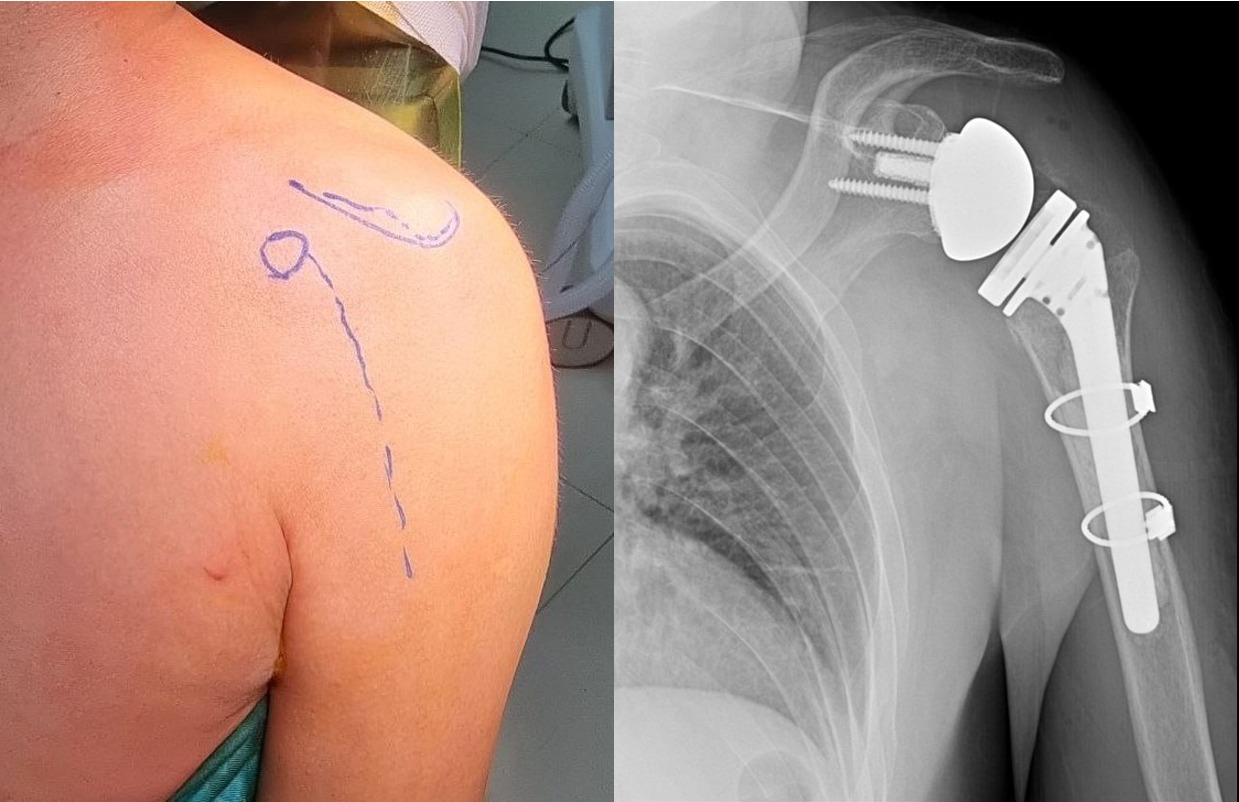

Гэмтэл согог судлалын үндэсний төвийн Гар сарвууны мэс заслын тасгийн хамт олон Монгол Улсад анх удаа мөрний үеийг бүтэн солих мэс заслыг амжилттай хийж, эмчилгээний шинэ технологи нэвтрүүллээ.

Гар сарвууны мэс заслын тасагт дээд мөчний хугарал, мултрал, дээд мөчний үе солих мэс засал, мөчдийн судас, мэдрэл, шөрмөсний гэмтлийн мэс засал, тасарсан мөч эргүүлэн залгах, яс зөөлөн эдийн дутмагшлыг нөхөн сэргээх бичил мэс заслаас гадна төрөлхийн болон олдмол согог засах мэс засал, мөчдийн яс, зөөлөн эдийн хавдар, үрэвслийн мэс заслын тусламж үйлчилгээг олон улсын түвшинд үзүүлж байна.